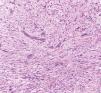

The nodule was excised with a shaving, and histopathology showed a monotonous proliferation of a fascicular pattern of spindle-shaped, pleomorphic cells, at times with a whirlwind pattern and interspersed with collagen fibers (Figure 2). Many mitotic figures were found (17 in 10 high power fields) (Figure 3). Immunohistochemistry was positive for smooth muscle actin (SMA) (clone 1A4) and negative for CD34 S100 protein (Figure 4). These findings allowed for the diagnosis of grade 3 leiomyosarcoma according to the Sarcoma Group classification of the Fédération Nationale des Centres de Lutte Contre le Cancer (FNCLCC), France.5

Leiomyosarcoma histopathology shows a spindle-shaped cell malignancy, with eosinophilic cytoplasm and nuclei with blunt edges (“cigar-shaped”). Most are well to moderately differentiated.7,8 Mitotic figures are easily found, especially in the deeper tumors.3,7 There are many differential diagnoses to be considered; immunohistochemistry is essential for an accurate diagnosis (Table 1).4